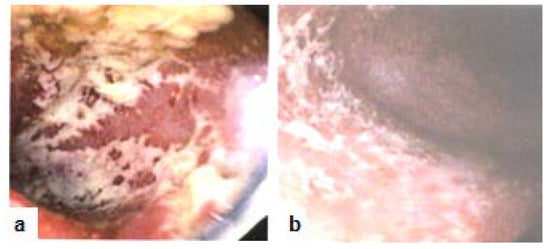

The patient is a 52 year old female, non-smoker, social alcohol user with a 30 years history of primarily left-sided colitis (Figure 1a,b, 2010). The patient was seen by her community primary care physician and was treated at various times with prednisone, several brands of mesalamine (e.g., Asacol HD® or Lialda® as dictated by insurance formularies), azathioprine (Imuran®), metronidazole (Flagyl®), and loperamide hydrochloride (Imodium®). Following multiple flare-ups with worsening symptoms which required a series of hospitalizations (2015), she was referred to the gastroenterologist (AC) for additional care management. The patient was being seen by primary care prior to this referral. The patient was started on golimumab (Simponi®), but after the fourth injection she was determined to be a primary non-responder, since her symptoms had deteriorated to pan-colitis. However, the levels of golimumab were not checked before.The patient experienced serial hospitalizations (2016) during which time she was treated with intravenous steroids, budesonide (Entocort®), rifaximin (Xifaxan®), metronidazole, probiotics VSL#3®, and mesalamine. On a follow-up visit after a hospitalization, (Remicade®, 5mg/kg/8wks) was initiated along with azathioprine(about 6 months later, in 2017). Her symptoms then improved temporarily, but soon relapsed with pan-colitis flares requiring repeated hospitalizations.Anser IFx® test revealed no antibody titers (0) with low infliximab level (6.1 μg/mL). Infliximab dosage was then increased (to 10mg/kg/4wks) in conjunction with a short course of budesonide (Uceris®) during 2017. This led to about six months of symptomatic improvement during which she was once treated for Clostridium difficile (C diff) infection.

Figure 1. Colonoscopy (2010) with image representatives. (a) Rectum: Ulcerative colitis; (b) Sigmoid colon: Ulcerative colitis.